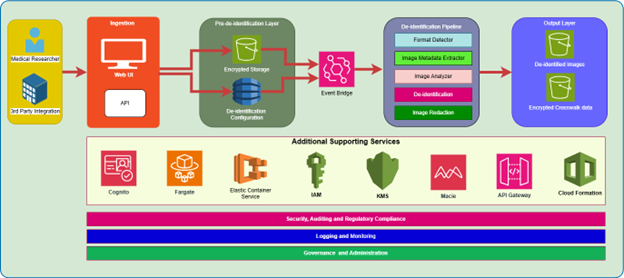

PixelGuard—built on Amazon Web Services (AWS) and created by Northwestern University Assistant Professor and Founder of Xtasis, LLC, Dr. Adrienne Kline—is an advanced software solution that deidentifies medical images while preserving clinical relevance and efficacy. It uses over 75 state-of-the-art AI-driven models capable of detecting and redacting multilingual, multi-orientation text across all major formats (DICOM, JPEG, PNG, NIfTI, etc.), alongside configurable metadata anonymization. With an intuitive UI, enterprise SSO, and in-tenant deployment (no data egress), PixelGuard delivers secure, compliant, and high-throughput image de-identification. PixelGuard is available on AWS Marketplace. ScaleCapacity—an AWS Partner—was instrumental in the development of the UI, cloud infrastructure, and deployment to AWS Marketplace.

Ingestion layer

The ingestion layer provides a user interface and an API to submit a medical image for de-identification. The API can also be used by a third-party medical device manufacturer to provide the redaction ability. Prior to the ingestion, the web UI and API can be secured with enterprise identity provider based authorization. Along with ingesting the image needing de-identification, this layer must also capture the specific de-identification configuration, which defines which fields need to be redacted from the image. For common redaction scenarios such as redaction to comply with HIPAA regulations, predefined field sets are defined and recorded.

Pre de-identification layer

The storage layer is used to store the image prior to the de-identification. Furthermore, the storage layer may also store a compressed file containing several images needing de-identification. Moreover, this layer also stores metadata pertaining to the de-identification job such as the job ID, submission time, specific fields being redacted, format of the file provided, etc.

Processing layer

The storage layer identifies the format of an image needing de-identification and based on the specific de-identification configuration, the image metadata defined by the DICOM tags and the Pixel-level de-identification is undertaken. Furthermore, the image can be compressed for storage optimization and a crosswalk file referencing a unique ID is created. The crosswalk file makes it possible to do a reverse lookup of the original file if it is ever needed. Care should be exercised to secure the crosswalk file and store it separate from the de-identified file.

De-identification pipeline

The de-identified storage layer stores the processed de-identified medical image, which can be used by medical researchers as part of a study. Furthermore, the image can be generated in various formats consistent with the needs of the research study.

De-identified output layer

The de-identified images can be created in conjunction with a crosswalk file that can maintain a mapping between an identifier in the de-identified image and a relevant identifier in the original image. The crosswalk file is maintained separately and encrypted to allow only authorized individuals to trace the de-identified image back to its original source if needed.

Auditing, monitoring, and observability

The auditing, monitoring, and observability layer stores access logs to make sure that records of who accessed what, when, and how can be stored for record keeping purposes. Furthermore, detailed error logs if any can be stored to enable troubleshooting if certain medical images could not be de-identified.

Tools and frameworks

Ingestion: The ingestion layer can be handled with a Web UI and an API that can be exposed through the API Gateway and that can perform request validation, authentication, and authorization along with security rule enforcement. The API Gateway integrates with Amazon Cognito to enforce fine-grained authentication and authorization.

Pre-de-identification storage: This layer can store pre-defined image de-identification profiles such as those for HIPAA, and can store it to an Amazon Simple Storage Service (Amazon S3) bucket or to a combination of an S3 bucket and Amazon DynamoDB.

De-identification: De-identification is a multi-step process that can use DICOM parser libraries such as pydicom and scrubbing tools such as dicom-anonymizer. Amazon Textract, and Amazon Comprehend Medical can also be used to identify embedded text within images.

Output: Post de-identification medical images can be compressed, converted to a different format, and stored with identifiers that can be mapped to the original source if needed. The storage can be handled with S3 buckets or file systems as needed with or without compression.

Other supporting services: Other supporting services play a critical role in enabling security, scalability, manageability, and infrastructure automation. Services such as Amazon API Gateway make it possible to enforce AuthN/AuthZ policies consistent with organizational needs. AWS Key Management Service (AWS KMS) provides a secure way to manage cryptographic keys and protect your data. AWS Fargate can be used to run thousands of containers without the need to manage servers or clusters of Amazon Elastic Compute Cloud (Amazon EC2) instances.

Furthermore, services such as Amazon Macie can add a secondary layer of protection to identify sensitive data and to protect it in conjunction with other remediation services. Moreover, services such as AWS CloudFormation enable the defining of AWS infrastructure resources in a declarative way, using templates in the JSON or YAML format and can automate the creation, configuration, and management of these resources, acting as an infrastructure as code (IaC) tool.